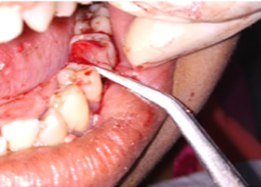

Half of Lower molar tooth along with diseased root removed & rest part is saved.

PRE OP Clinical Photograph Measuring Probing Depth